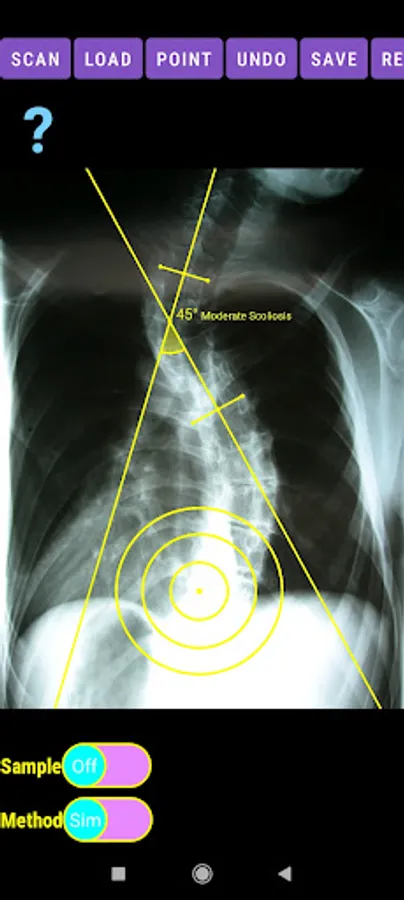

-Offers a very convenient way to determine the most accurate possibly way at once. By marking four points at the same X-ray, at each spine the App calculates the Cobb angle. In cases where values are out of normal ranges, the scoliosis is categorized according to measured angle as mild, moderate, severe. To simplify the process and to minimize inter-observer errors usually by not selecting the actual end vertebra, the app offers also in ext mode the ability to draw the vertical reference line through the patient’s sacrum and to identify more easily the end vertebrae (ext method).

The app offers a very convenient way to asses spinal deformity by measuring the Cobb angle. The first thing is to load one image from your photo library or capture a photo from x-rays photos of a patient. The app offers two measuring methods, the simple (Sim.) and the extended (Ext.). By clicking the relevant option, the option is highlighted and the respective method is activated.